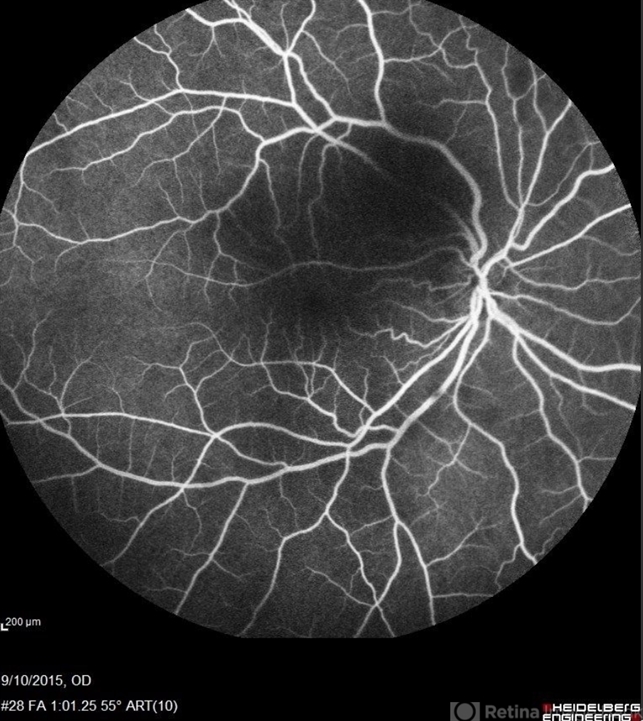

- Sickle Cell Retinopathy

- sickle cell retinopathy, peripheral retinal neovascularization, sea fan

- Scanning laser ophthalmoscope

- Angiography showed normal vessels posteriorly but severe capillary drop out throughout the periphery OU with scattered severe neovascularization at the edge of the capillary drop out peripherally.